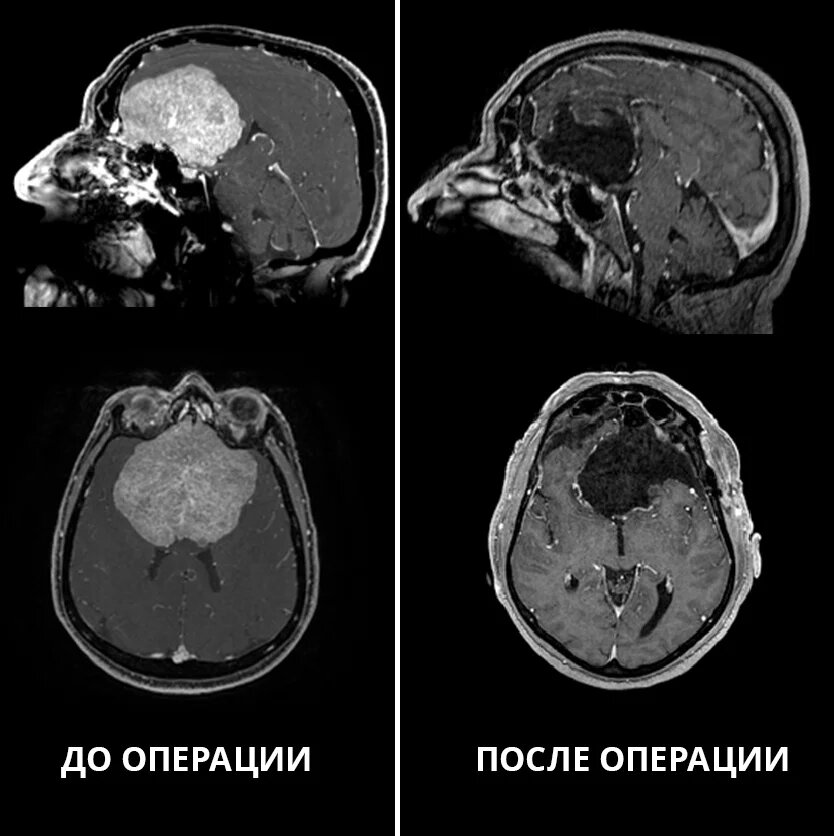

Также пациент пожаловался на отсутствие обоняния, плохую память и зрение, ослабление самокритики и постоянно приподнятое без причины настроение. В ходе обследования врачи выявили истинную причину этих симптомов: гигантскую опухоль головного мозга.

«Менингиома диаметром 8,5 см располагалась в области передней черепной ямки и очень сильно сдавливала обе лобные доли. Такие большие размеры менингиом в настоящее время встречаются крайне редко. Кроме того, по поверхности опухоли и частично в её капсуле проходили крупные магистральные артерии головного мозга: обе внутренние сонные артерии с их ветвями, обе передние мозговые артерии, передняя соединительная артерия, а также – оба зрительных нерва и их перекрёст (хиазма).Повреждение любой из этих артерий или нервов могло привести к самым неблагоприятным последствиям: инсульту, кровотечению, слепоте, тяжёлым нарушениям обмена веществ. Нам предстояло многочасовое, очень кропотливое вмешательство высокого риска, требующее предельной концентрации».

В ходе 8-часовой операции Сергею Чернову удалось полностью удалить опухоль и сохранить все анатомические структуры. Образование оказалось доброкачественным.